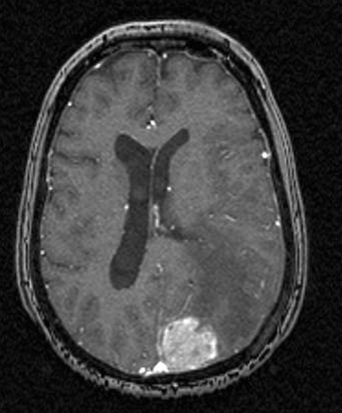

Hjerne, Metastase, MR-scanning

MR-scanning med kontraststof viser en metastase fra en kræftknude i brystet. Man ser den både axialt og saggitalt.

Gengivet med tilladelse fra Radiologisk afdeling, Universitetssygehuset Nord-Norge